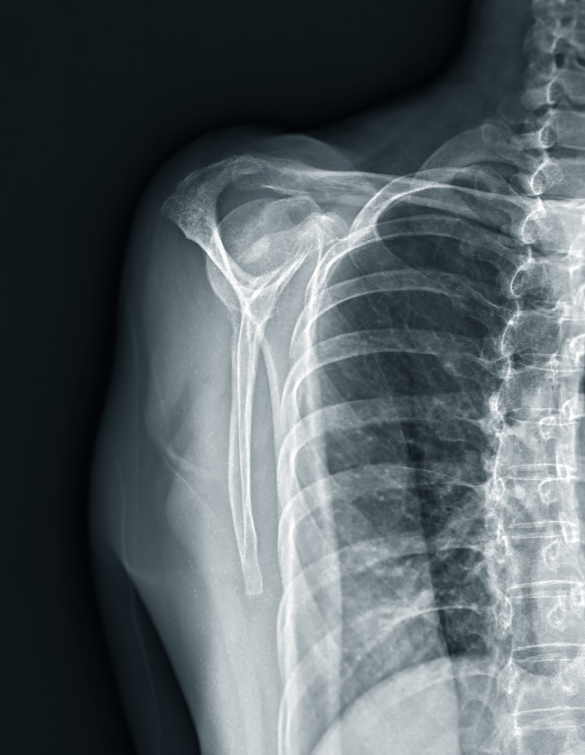

Shoulder joint replacement, also known as shoulder arthroplasty, is a surgical procedure in which damaged parts of the shoulder joint are replaced with artificial components to restore function and relieve pain. It is primarily recommended for patients suffering from severe shoulder arthritis, complex fractures, or long-standing rotator cuff injuries that have led to joint deterioration. The procedure can be total (replacing both the ball and socket), partial (replacing only the humeral head), or reverse (used when rotator cuff muscles are non-functional).

Our center provides comprehensive shoulder replacement services, starting with advanced diagnostics such as digital X-rays, CT scans, and MRI to evaluate joint damage and determine the appropriate type of replacement. We offer total shoulder replacement for arthritis, partial shoulder replacement for isolated humeral head damage, and reverse shoulder replacement for patients with irreparable rotator cuff tears.